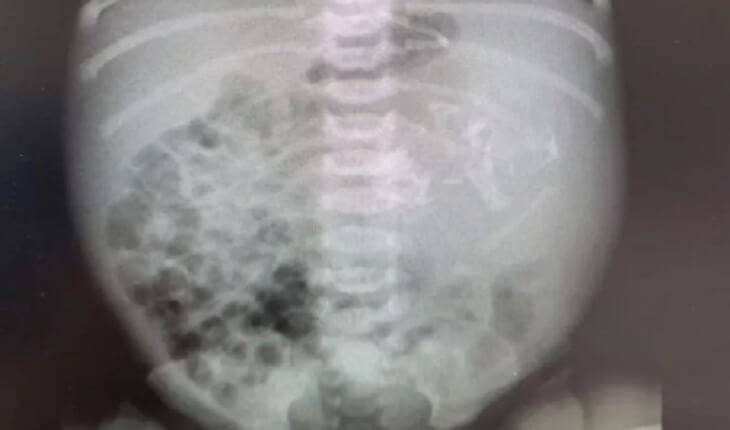

Bebê nasce com embrião dentro da barriga e deixa médicos chocados

O caso raríssimo ocorreu em Israel no início deste mês e a chance é de um a cada 500 mil nascimentos.